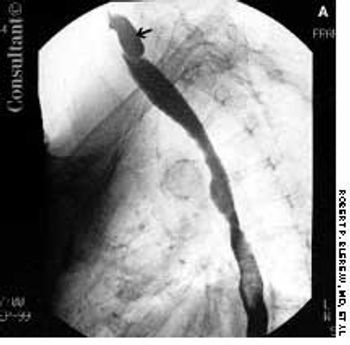

For 2 months, food particles had been regurgitating into a 72-year-old woman's throat after meals. Barium esophagography revealed a Zenker, or pharyngoesophageal, diverticulum.